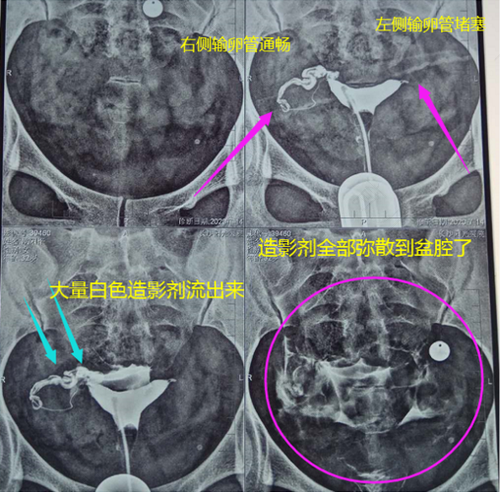

输卵管造影其实就是现在医学临床上运用广泛的一种检查,它就是为了方便检测女性输卵管是否通常。检查过程中注入的造影剂会在72小时内排出体外。

这项技术很多女性在听到造影剂不能被人体吸收,心里就会咯噔一下。其实备孕的女性们不用太过担心,因为这项技术早在20年代就已经被我们国家采用了,造影技术不仅仅可以知道输卵管是否通畅,而且也可以明确堵塞位置。在整个过程中也不需要麻醉,并且非常安全,深受很多患者的好评。但是也有一些人不适合做造影的: